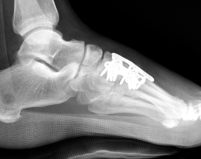

X-ray

Subtle widening of the medial cuneiform - 2nd metarsal distance, and the inter-metatarsal distance

Widening of the medial cuneiform - 2nd metatarsal distance, inter-metatarsal diastasis, fleck sign, possibly increased inter-cuneiform distance

Widening of the medial cuneiform - 2nd metatarsal distance, inter-metatarsal diastasis, fleck sign, increased inter-cuneiform distance